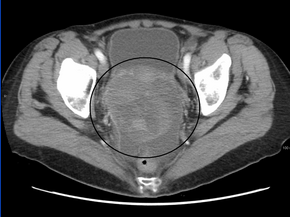

CT scanning is preferred to assess the extent of the tumor in the abdominopelvic cavity, though magnetic resonance imaging can also be used.[21] CT scanning can also be useful for finding omental caking or differentiating fluid from solid tumor in the abdomen, especially in low malignant potential tumors. However, it may not detect smaller tumors. Sometimes, a chest x-ray is used to detect metastases in the chest or pleural effusion. Another test for metastatic disease, though it is infrequently used, is a barium enema, which can show if the rectosigmoid colon is involved in the disease. Positron emission tomography, bone scans, and paracentesis are of limited use; in fact, paracentesis can cause metastases to form at the needle insertion site and may not provide useful results.[22] However, paracentesis can be used in cases where there is no pelvic mass and ascites is still present.[22] A physician suspecting ovarian cancer may also perform mammography or an endometrial biopsy (in the case of abnormal bleeding) to assess the possibility of breast malignancies and endometrial malignancy, respectively. Vaginal ultrasonography is often the first-line imaging study performed when an adnexal mass is found. Several characteristics of an adnexal mass indicate ovarian malignancy; they usually are solid, irregular, multilocular, and/or large; and they typically have papillary features, central vessels, and/or irregular internal septations.[24] However, SCST has no definitive characteristics on radiographic study.[25]

Ovarian cancer is staged using the FIGO staging system and uses information obtained after surgery, which can include a total abdominal hysterectomy via midline laparotomy, removal of (usually) both ovaries and Fallopian tubes, (usually) the omentum, pelvic (peritoneal) washings, assessment of retroperitoneal lymph nodes (including the pelvic and para-aortic lymph nodes), appendectomy in suspected mucinous tumors, and pelvic/peritoneal biopsies for cytopathology.[21][19][24][53] Around 30% of ovarian cancers that appear confined to the ovary have metastasized microscopically, which is why even stage-I cancers must be staged completely.[19] 22% of cancers presumed to be stage I are observed to have lymphatic metastases.[24] The AJCC stage is the same as the FIGO stage. The AJCC staging system describes the extent of the primary tumor (T), the absence or presence of metastasis to nearby lymph nodes (N), and the absence or presence of distant metastasis (M).[54] The most common stage at diagnosis is stage IIIc, with over 70% of diagnoses.[19]

Stage 1 ovarian cancer

Stage 2 ovarian cancer

Stage 3 ovarian cancer

Stage 4 ovarian cancer